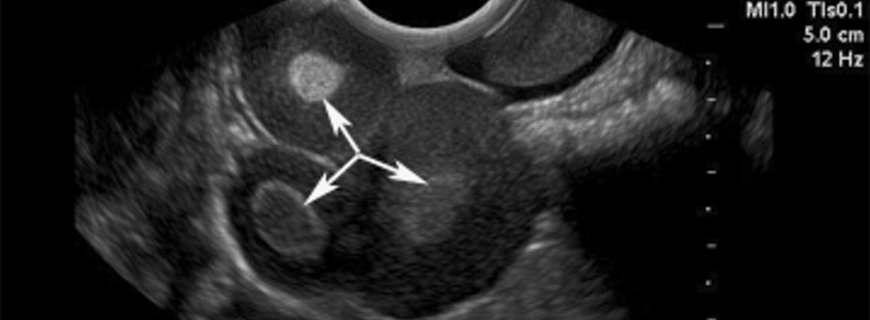

Devamını OkuYumurtalık Kitleleri Nasıl Değerlendirilir?

İlgili belirtilerin ve daha önce belirtilen risk faktörlerinin sorgulanmasını içeren bir hikaye alınır ve genel fizik muayene yapılır. Yumurtalık kanseri ile ilgili genel fizik muayene bulguları, akciğerde sıvı birikimi, karında sıvı birikimi veya k...